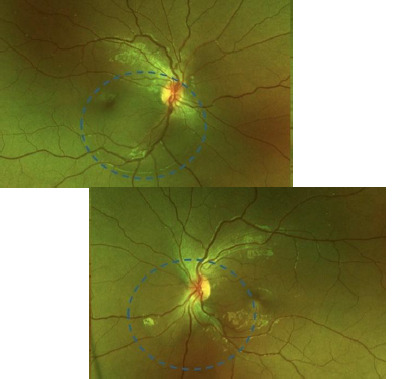

Results: A 14-year-old girl with no significant medical history reported several weeks of blurred vision in both eyes. She had been using 2% topical minoxidil on her eyebrows and eyelashes without a prescription for the past 6 months. The initial examination revealed that the best-corrected visual acuity (BCVA) was 20/80 in the right eye and 20/25 in the left eye, with no abnormalities noted in the anterior segment. Fundus evaluation and OCT confirmed bilateral serous retinal detachment. Given the patient's unsupervised minoxidil use, a causal link to central serous chorioretinopathy (CSC) was suspected. After discontinuing the drug, the subretinal fluid (SRF) resolved, and visual acuity fully recovered within three months, supporting the association between minoxidil and choroidal neovascularization (CNV), not CSC.